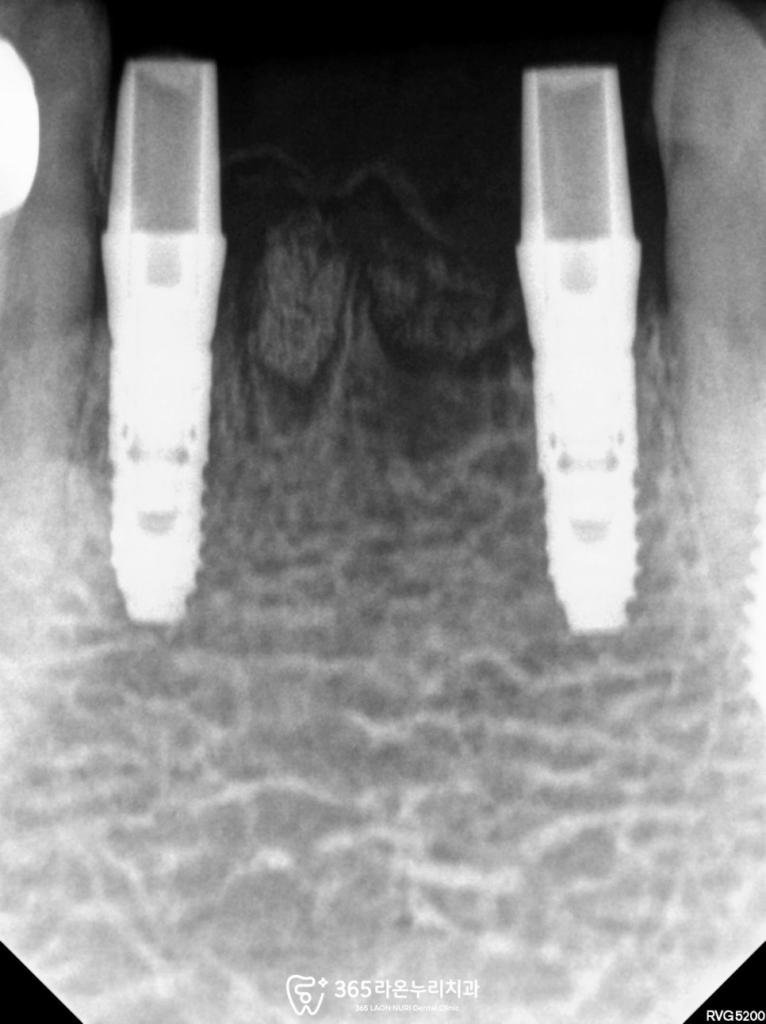

검진 결과

아래쪽 앞니 뿌리 주변으로

염증이 나타난 것을

확인할 수 있었습니다.

그로 인해 치조골이 녹아서

내려가 있는 모습을 확인 할 수 있습니다.

수립된 계획에 맞춰 32, 42 앞니 발치 후

픽스처 식립 및 골유착이 이뤄나도록

Healing Abutment로 덮어줍니다.

2025.4.23